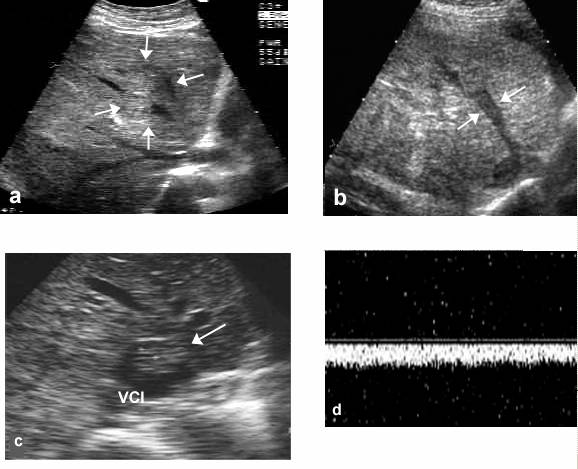

Modele ecografice de tromboza maligna a venelor hepatice: a. invazie tumorala intrahepatica (sageti); b. tromboza maligna a venei hepatice medii (sageti); c. tromboza intrahepatica cu prolabare in vena cava inferioara; d. spectru venos monofazic

Explorarea poate detecta extensia procesului tumoral la nivelul venei cave inferioare (c). Examinarea codificata color usureaza considerabil diagnosticul, prin demonstrarea disparitiei semnalului din venele hepatice. In obstructiile venoase incomplete, se constata disparitia semnalului trifazic si aparitia unui semnal vascular monofazic (d). Hepatocarcinomul incipient este definit ca un nodul malign unic, dezvoltat frecvent pe ficat cirotic, avand diametrul sub 2 cm. Aceasta varianta de hepatom este vindecabila chirurgical sau prin alte tehnici terapeutice (embolizare, alcoolizare etc.). Clinic, HCC incipient este asimptomatic, iar biologic poate evolua cu valori crescute ale alfa-1-fetoproteinei si a unor markeri tumorali nespecifici (gamaglutamiltranspeptidaza, fosfataza alcalina etc.). Performanta diagnostica a ecografiei in detectarea HCC se caracterizeaza printr-o sensibilitate de 58,9% si o specificitate de 99,9%. Rata detectarii sonografice a HCC sub 3 cm poate ajunge la 91,2 % din cazuri atunci cand explorarea se efectueaza sistematic, sub forma de studii screening efectuate la intervale de 6 luni, pe populatii cu risc. Ecografic, HCC incipient se prezinta ca o formatiune nodulara unica, rotunda, relativ bine delimitata, hipoecogena, avand consistenta parenchimatoasa ( a,b).

Diagnosticul diferential al trombozei portale maligne trebuie facut cu situatiile in care fluxul sangvin portal este foarte lent si devine ecogen. Explorarea ecografica codificata color, indeosebi in modul power, precum si administrarea agentilor de contrast intravenos usureaza diagnosticul. Tromboza portala benigna, hematica, poate mima o invazie portala tumorala atunci cand este veche si devine ecogena. Diagnosticul se poate transa prin punctie aspirativa dirijata in tromb sau prin urmarirea ecografica la intervale de 6 - 12 saptamani. In caz de tromboza hematica, aspectul ecografic se modifica de la o explorare la alta. Apar semne de recanalizare si, tardiv, se poate constitui un cavernom portal. Invazia venelor hepatice de catre HCC este vizibila ecografic in sub 10% din cazuri. Aspectul poate fi acela de obliterare luminala completa, prin colabare datorita unui proces extrinsec (fig. b) sau prin ecouri intravasculare (fig. a).